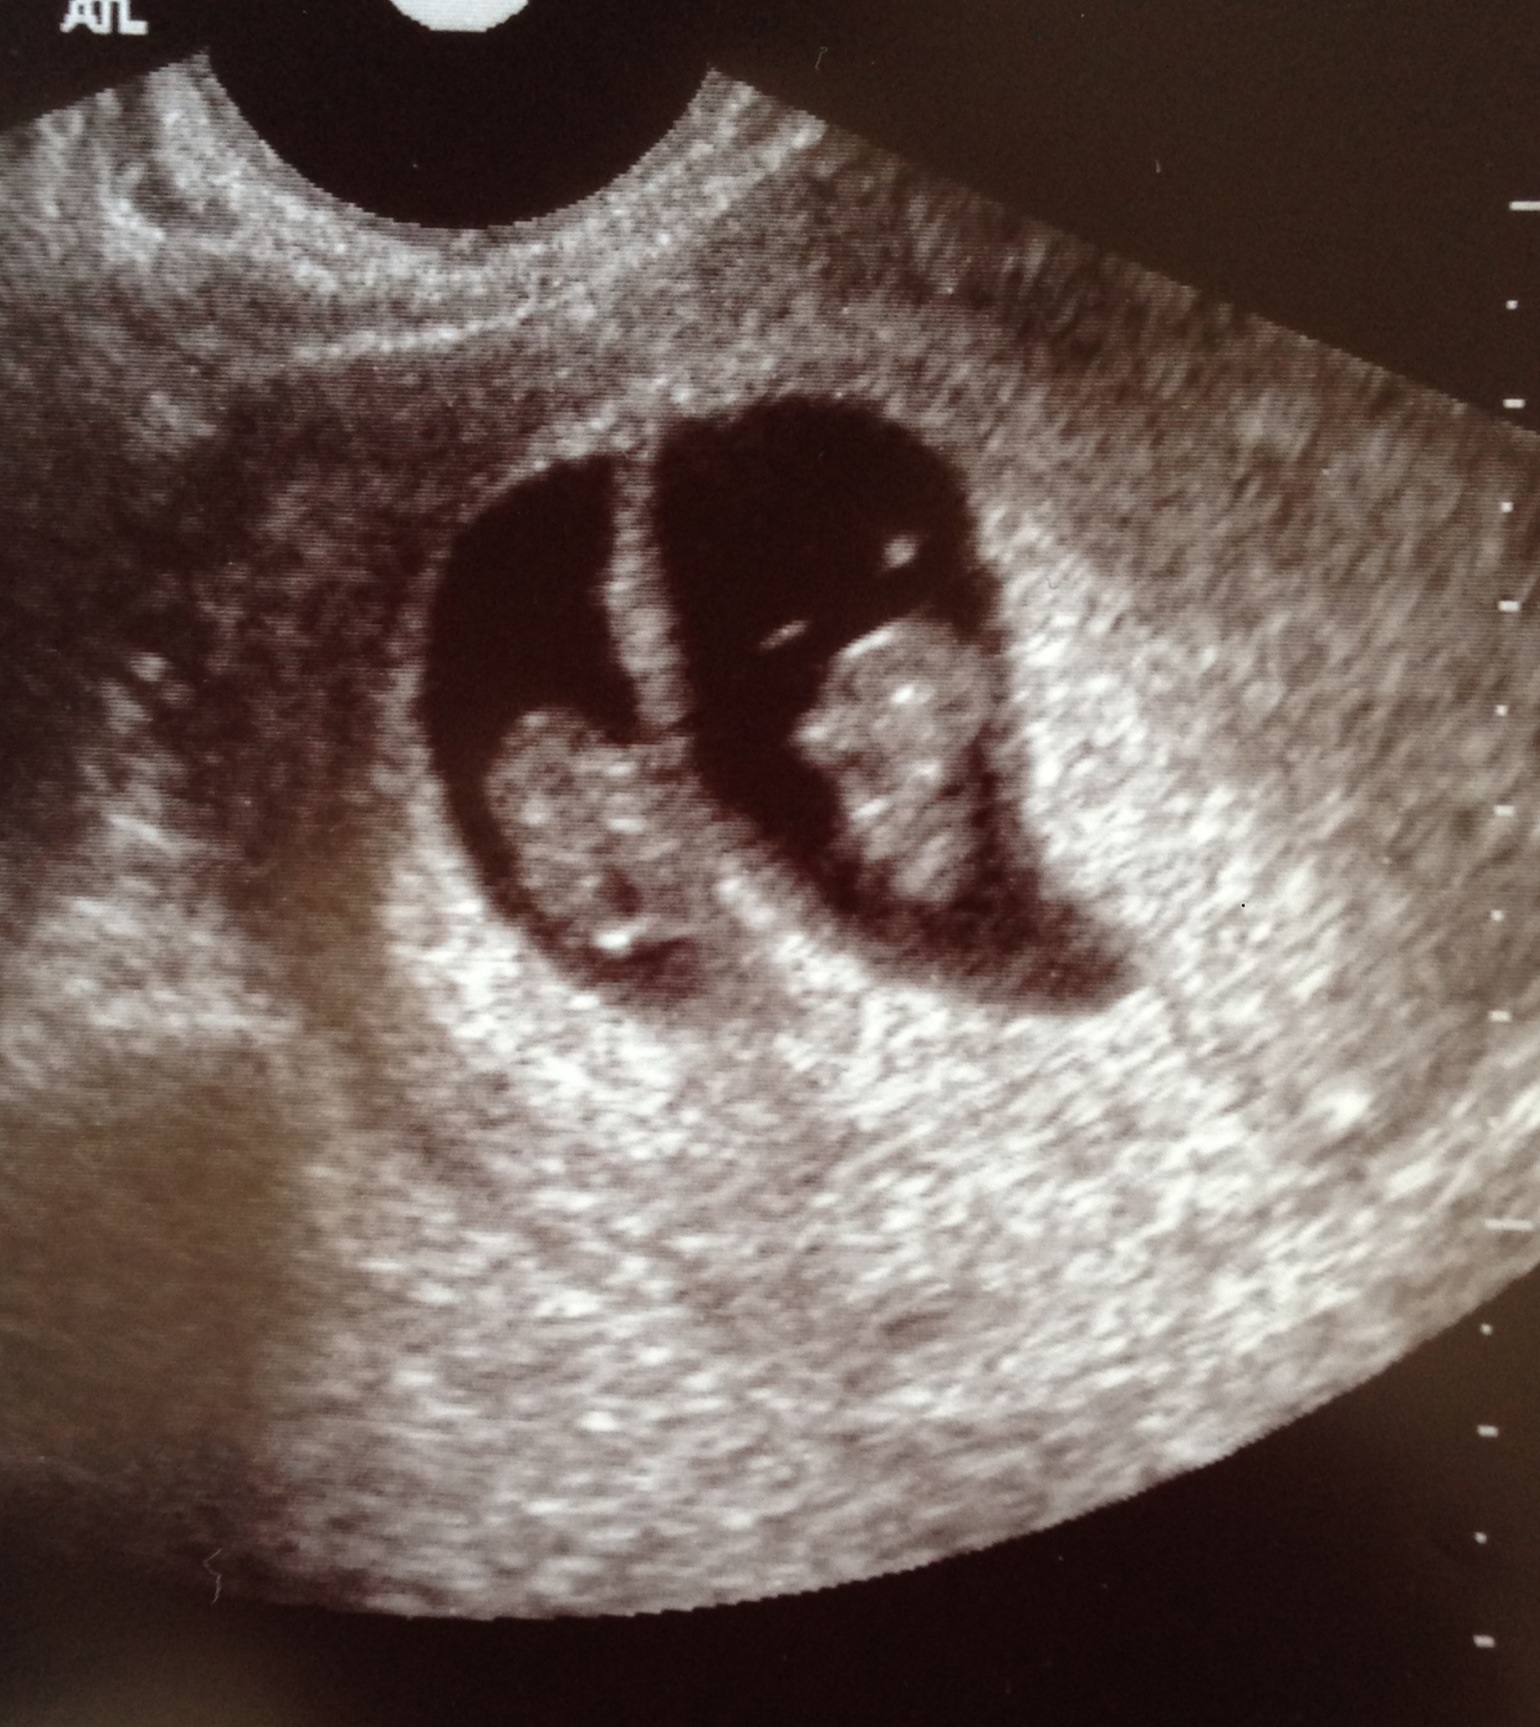

Here's my pic of my twins at 7w. It was super obvious there were two in there (di/di). I know the beans are tiny, but they're there (the tech wasn't the greatest, so the pics we got weren't super clear). Even at the u/s, she was like "here's your baby" then I had to be like "umm, what's that other one?" and she said "that's the other one," so it was clear to me right away. I hope you get some clear answers soon though! Sucks not knowing for sure, but to me it looks like one.

ETA: Of course I JUSt read the update the OP posted! Congrats on the healthy little bean! :)